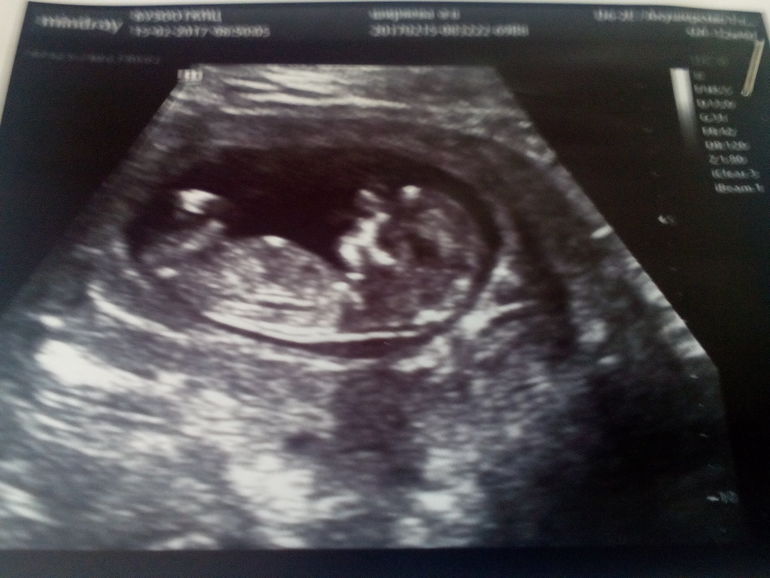

На УЗИ в ходе первого скрининга женщина сможет увидеть своего малыша . Для многих — это первая встреча с крохой . Ребенок, который перестал быть эмбрионом и стал плодом, сможет порадовать . . .

Во время первого скрининга нормальные значения КТР следующие: на 10 неделе - 24-38 мм; на 11 неделе - 34-50 мм; на 12 неделе — 42-59 мм; на 13 неделе — 51-75 мм .

Первый скрининг проводится в первом триместре . 1 триместр - это с 1 по 14 неделю беременности . Соответственно, сроки проведения первого скрининга при беременности - в период с 11 по 14 неделю .

Врачи говорят, что идеальное время для первого скрининга - это 11-12 неделя . Вы вместе с вашим врачом должны предельно точно рассчитать время скрининга, учитывая дату последней менструации .

Первый скрининг, скрининг первого триместра - сроки, подробности, результаты вы найдёте в этой статье . Скрининг первого триместра включает в себя: 1 . Исследование УЗИ (причем, многие лаборатории запрашивают . . .

Недели первого скрининга выбраны неспроста . Раньше 10-й недели плод слишком мал, чтобы определить данный параметр . Позже 14-й недели исследование шейной складки становится неинформативным . . .